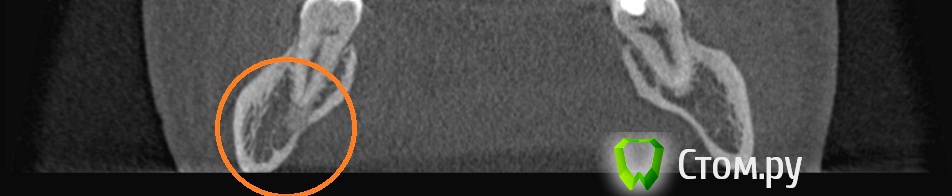

winnt Опубликовано 18 июля, 2014 Автор Поделиться Опубликовано 18 июля, 2014 То есть 7ой зуб чувствует холод? Болит меньше когда прикладываете? А скололся скорее всего из-за кариеса, антогонист скол не вызовет, либо стираемость может быть и увеличение чувствительности. Пломбу вам случаем не завысили?Холод чувствует, но как-то тупее чем здоровый зуб и боль остается дольше после холодного;Когда прикладываю болит больше и после того как убираю боль "остается" дольше чем в здоровом;Скололся от удара нижней челюстью об торпеду авто;Пломбу не завысили, это точно. Покрутил в КТ этот зуб и стало чуть страшно будто от корня этого зуба "что-то растет" прямо в НЧ.канал: Ссылка на комментарий

Гарриевич Опубликовано 18 июля, 2014 Поделиться Опубликовано 18 июля, 2014 на последнем снимке остеит, то есть хронические периапикальные изменения есть. скорее всего травма вызвала ответную реакцию пульпы зуба и ее частичное поражение. желательна конечно очная консультация 1 Ссылка на комментарий

winnt Опубликовано 18 июля, 2014 Автор Поделиться Опубликовано 18 июля, 2014 на последнем снимке остеит, то есть хронические периапикальные изменения есть. скорее всего травма вызвала ответную реакцию пульпы зуба и ее частичное поражение. желательна конечно очная консультация Спасибо Гарриевич, нашел описание в сети, все сходиться: condensing osteitis( focal sclerosing osteomyelitis) даже пишут, что чаще всего встречается на молярах НЧ.Вот только вопрос не может ли остеит в моем случае "вырасти в канал", или он распространяется только по структуре кости и скорей всего обойдет канал вокруг чем попадет внутрь? Как вы думаете есть показания к эндо в моем случае, наверное если не беспокоит зуб то с такой проблемой можно его не трогать, но в моем случае он "достает" меня очень долго и это похоже на что-то хроническое? Winnt, вашу бы энергию, да в мирное бы русло. Сходите к другому врачу, пусть пробу эндофростом проведет, и ЭОД. Эндофростом делали пробу - реакция есть, боль уходила довольно быстро, я и сам пробовал только вместо спец баллончика, брал для заправки зажигалок.Вот насчет ЭОД звонил пару врачам говорят нет, поищу еще, если не найду то куплю себе китайский.red_butler может быть такое что термо пробы не могут показать например хронический пульпит, другие изменения в переапикальной области. когда уже в пульпе пошли необратимые изменения и нужно эндо, а ЭОД покажет? Ссылка на комментарий